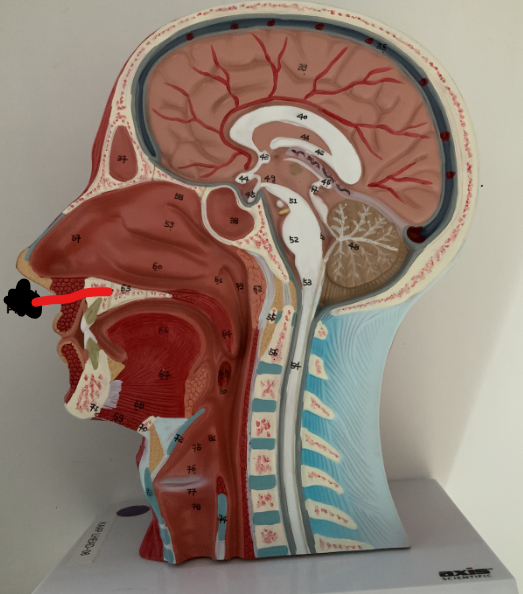

What structure is this?

Hard Palate